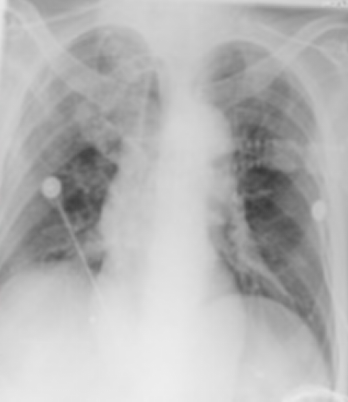

床旁胸片

• 右肺少许渗出影(图3

为什么会出现呼吸机依赖以呼吸困难首诊的肌萎缩侧索硬化症及呼吸机依赖原因分析_https://www.jmylbn.com_新闻资讯_第7张

3  床旁胸正位片(2018-07-15)